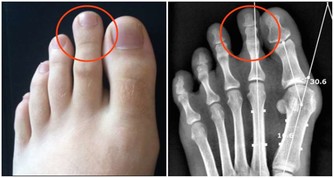

高尿酸、痛風,能吃豆腐嗎?要想遠離痛風,這3物需儘早撤下飯桌

痛風,幾乎也是讓大家聞之色變的一類疾病了,因為一旦患上了痛風,不僅身體會長時間受到折磨,精神上也會感到十分痛苦,而且在痛風患者的日常生活中,稍有不慎就可能會導致其他病症一齊發作。

所以,對於痛風,大家一定要有相關的防範意識,不要等到疾病纏身了,才知道後悔,尤其是平時在飲食中經常攝入高嘌呤食物,且尿酸水平持續偏高的人,更是要注意預防。